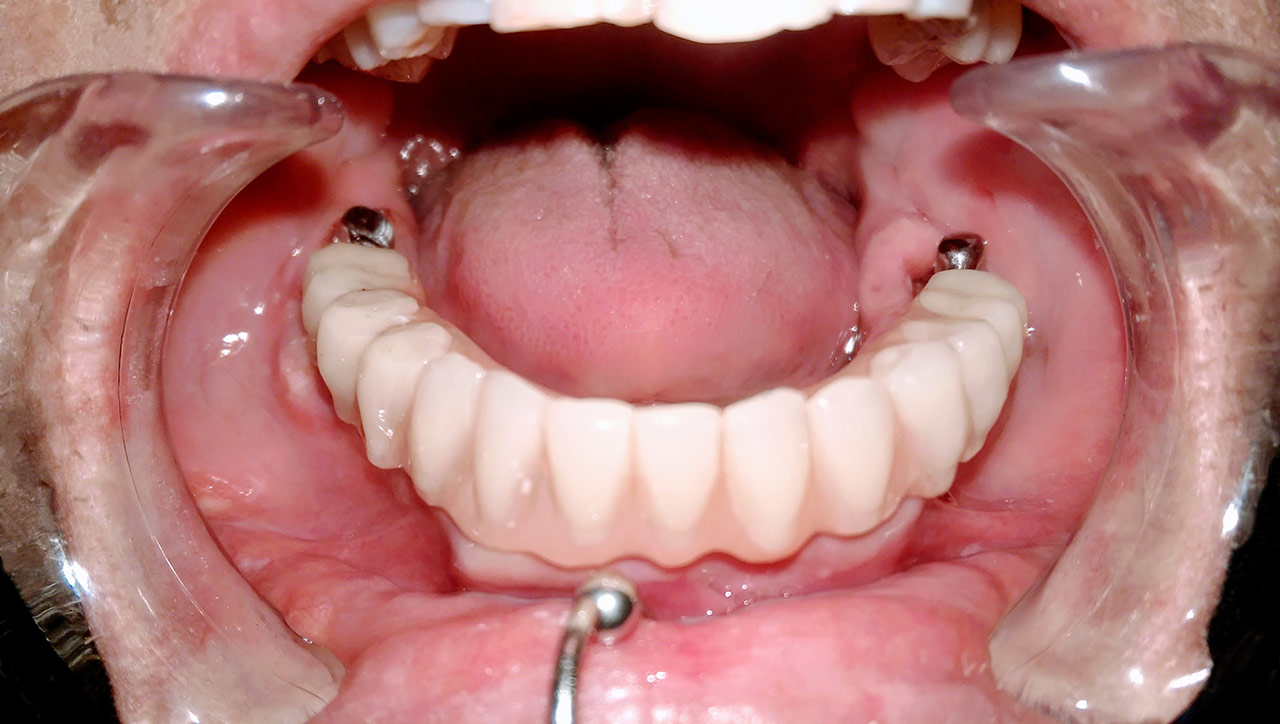

Alsó állcsont teljes rehabilitációja 72 óra alatt

Alsó állcsont teljes rehabilitációja 72 óra alatt, azonnal terhelhető implantátumokkal súlyos paradontitisben szenvedő dohányzó páciens esetében. Az alsó állcsont fogai mind mozogtak az előrehaladott fogágypusztulás miatt.

A fogakat eltávolítottuk, a gyulladt, fertőzött csontot kitakarítottuk, kifertőtlenítettük, majd azonnal implantáltunk.

Svájci, IHDE márkájú, azonnal terhelhető implantátumokat helyzetünk be, és ezekre harmadnapra rögzített, hosszútávú, fémvázas, esztétikus műanyaggal leplezett hidat ragasztottunk be.

Ezt az ideiglenes hidat a sebek gyógyulása miatt használjuk, de tartóssága miatt véglegesként is használható. A legtöbb esetben, ahogy itt is, 6 hónap múlva porcelán hídra cseréljük, a teljes gyógyulás után.